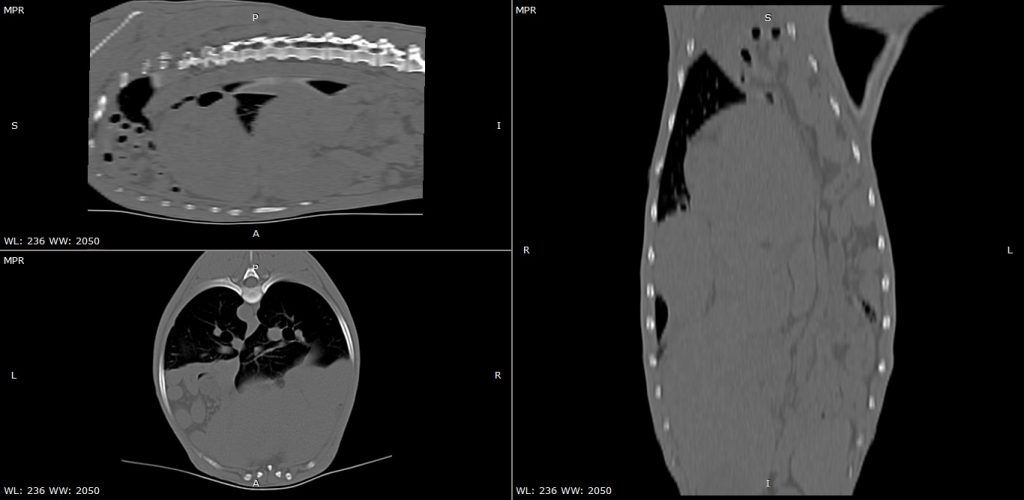

Decidieron realizar un TC porque no entendían que estaba ocurriendo.

Se observó una pérdida de continuidad del límite toraco-abdominal en el lado izquierdo (rotura del diafragma), con desplazamiento de las vísceras abdominales dentro de la cavidad torácica.

En la TC se aprecia el parte del contenido abdominal dentro de la cavidad torácia. Lo más llamativo son las asas intestinales localizadas por delante del corazón.